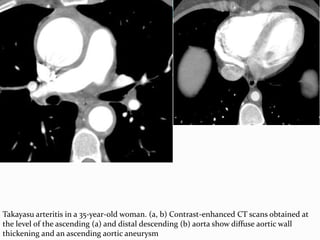

NON INFECTIVE AORTITIS

 rheumatoid arthritis, ankylosing spondylitis, giant cell

arteritis, and relapsing polychondritis commonly affect the

ascending aorta.

 In rheumatic fever the involvement can be segmental,

limited to the ascending aorta, involve the abdominal

aorta, or involve the entire aorta.

 Takayasu arteritis commonly affects the aortic arch and its

major branches, with variable involvement of the

abdominal aorta and pulmonary arteries.

 CT features include high attenuation of the thickened

aortic wall with calcifications on nonenhanced scans.

 Arterial enhancement is considered a sign of active disease

Takayasu arteritis in a 35-year-old woman. (a, b) Contrast-enhanced CT scans obtained at

the level of the ascending (a) and distal descending (b) aorta show diffuse aortic wall

thickening and an ascending aortic aneurysm